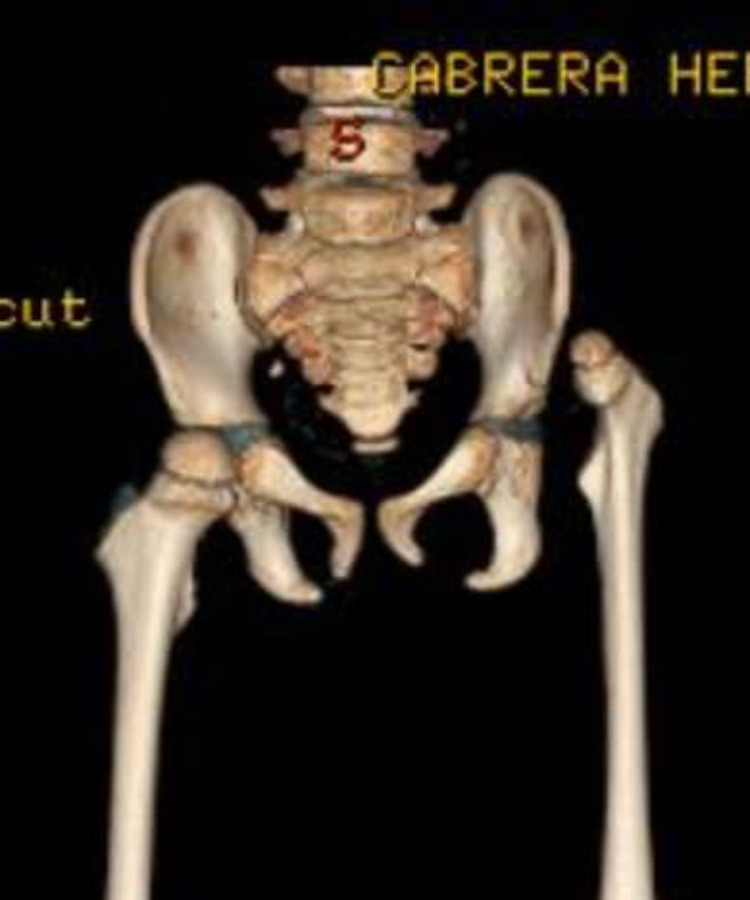

conocer másLa artrogriposis congénita causa rigidez articular, mientras que la displasia de cadera implica un desarrollo incorrecto de la articulación.